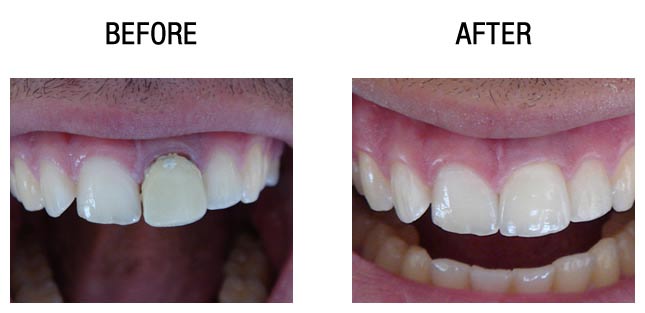

种植牙前后对比

种植牙前后对比